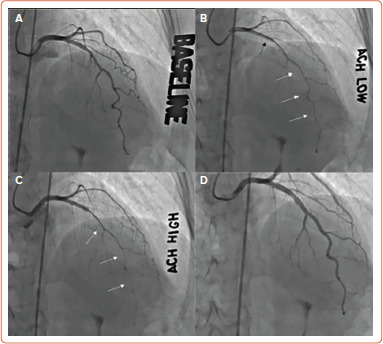

Vasospastic angina (VSA) occurs at rest and on exertion, with transient electrocardiographic ischemic changes. VSA presents with spontaneous coronary artery spasm (CAS); it has been associated with stable angina, acute coronary syndromes, and sudden cardiac death. CAS can be identified in normal arteries or non-obstructive coronary atherosclerosis, but is also prevalent in patients with coronary artery disease. The diagnosis is made with invasive coronary reactivity testing with provocation using acetylcholine (Ach). Epicardial spasms can be visualized through coronary angiography as a reversible epicardial vessel narrowing, while the diagnosis of microvascular spasm can be made when angina symptoms and ECG changes happen following intracoronary Ach without epicardial spasm. Identification of CAS allows for risk stratification and specific therapies targeting endothelial dysfunction and paradoxical vascular smooth muscle cell constriction. Therapies include calcium channel blockers as monotherapy or in a combination of a dihydropyridine and non-dihydropyridine. Short-acting nitrates offer acute symptomatic relief but long-acting nitrates should be used sparingly. This current update on invasive evaluation of VSA discusses unified Ach protocols.